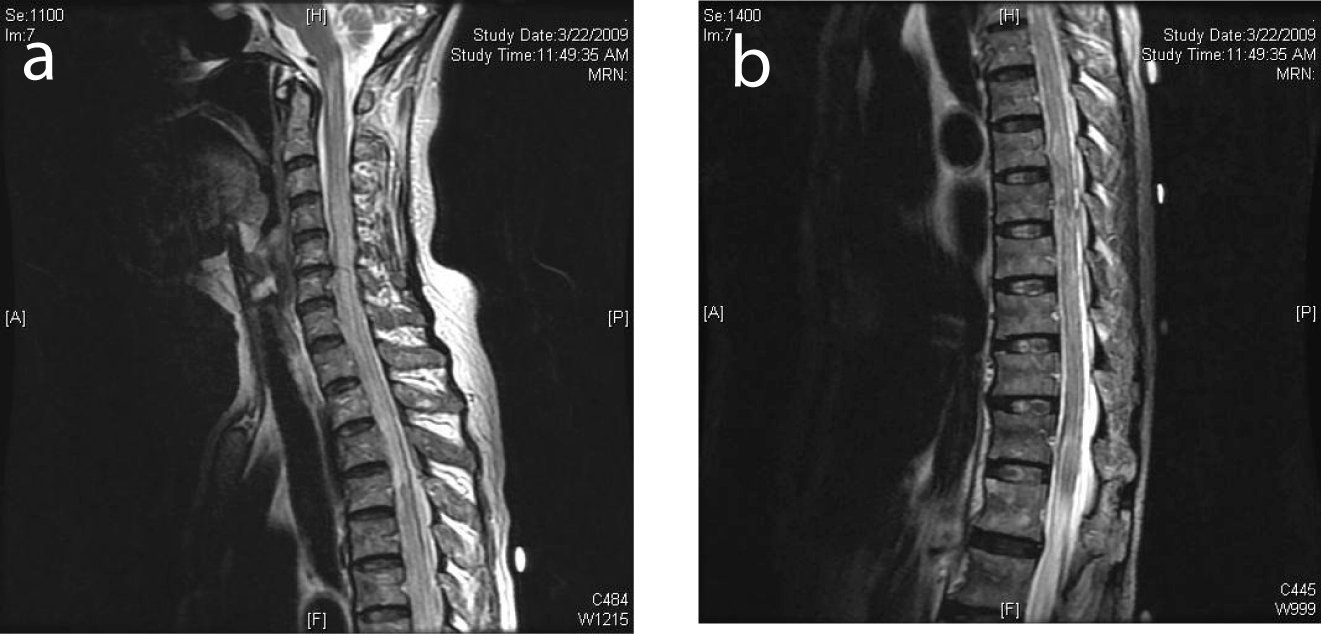

With no neurological improvement, a repeat MRI of the spine obtained a week later showed a long segment of T2-weighted hyperintensity and swelling of the spinal cord with abnormal enhancement from T6 level down to the conus medullaris (Fig. 2). Appearance was compatible with myelitis. Work-up for infective and autoimmune causes was initiated. Blood, CSF microscopy and serology were negative for cytomegalovirus, herpes simplex virus, Ebstein-Barr virus, fungi, and acid-fast bacilli. CSF viral and bacterial cultures were negative. Autoimmune markers, including the neuromyelitis optica (NMO) antibodies, were negative. CSF was again negative for malignant cells. Spinal cord infarct was thought to be less likely due to the long-segment contiguous involvement and lack of significant atherosclerotic disease elsewhere. Decision was made to continue observation as there was no worsening of her neurological deficit clinically.

![]() Click for large image | Figure 2. (a) MRI of the spine 1 week after presentation showed diffuse high T2 signal from the spinal cord from T6 to the conus compatible with cord edema. (b) Selected corresponding axial MR image showed edema across the whole cross-section of the spinal cord. |